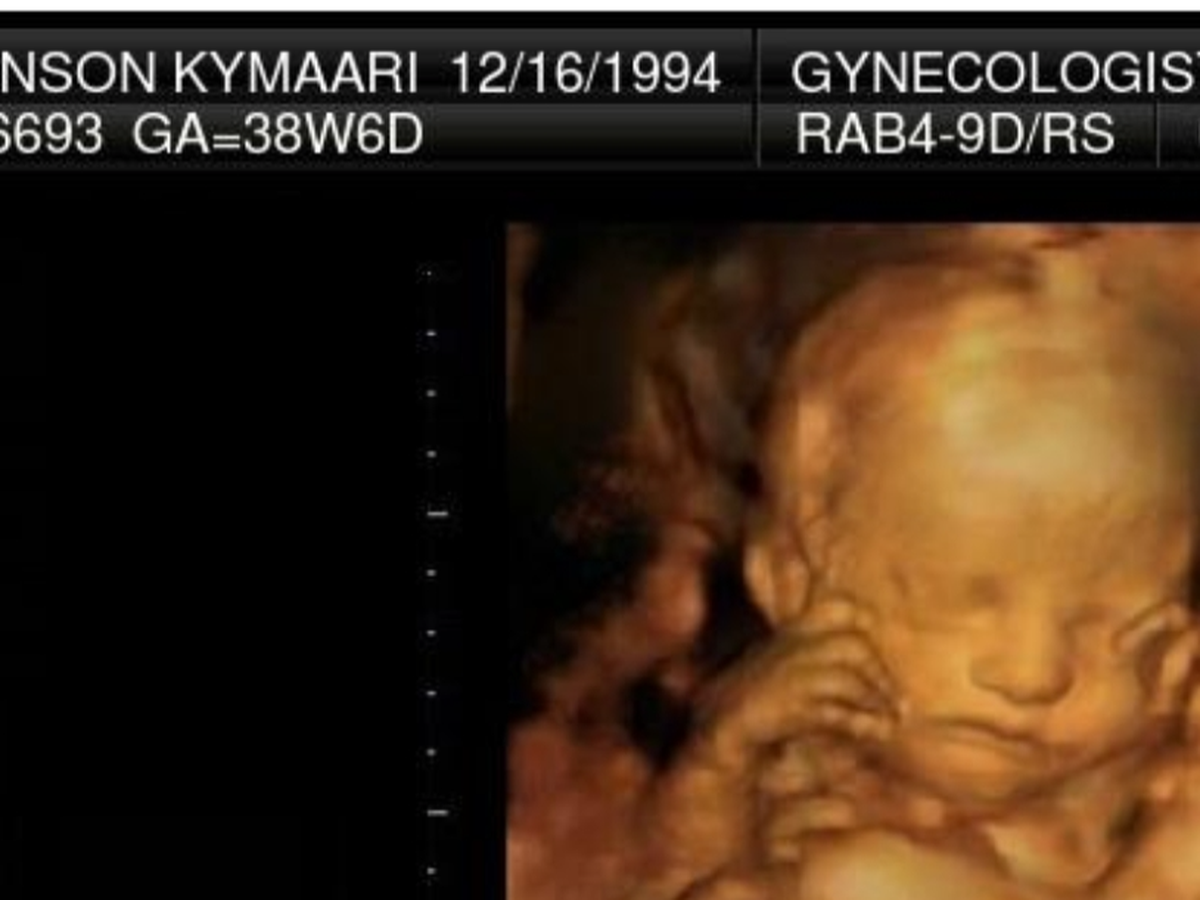

Hi im asking for help in getting my daughter cremated that i lost recently she was a still birth and we are trying to bring her home with us , anything would help